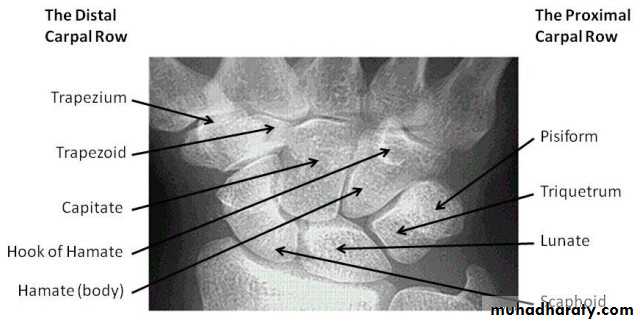

CARPAL BONES

FRACTURED SCAPHOID

Scaphoid fractures account for almost 75 per cent of all carpal fractures although they are rare in the elderly and in children.